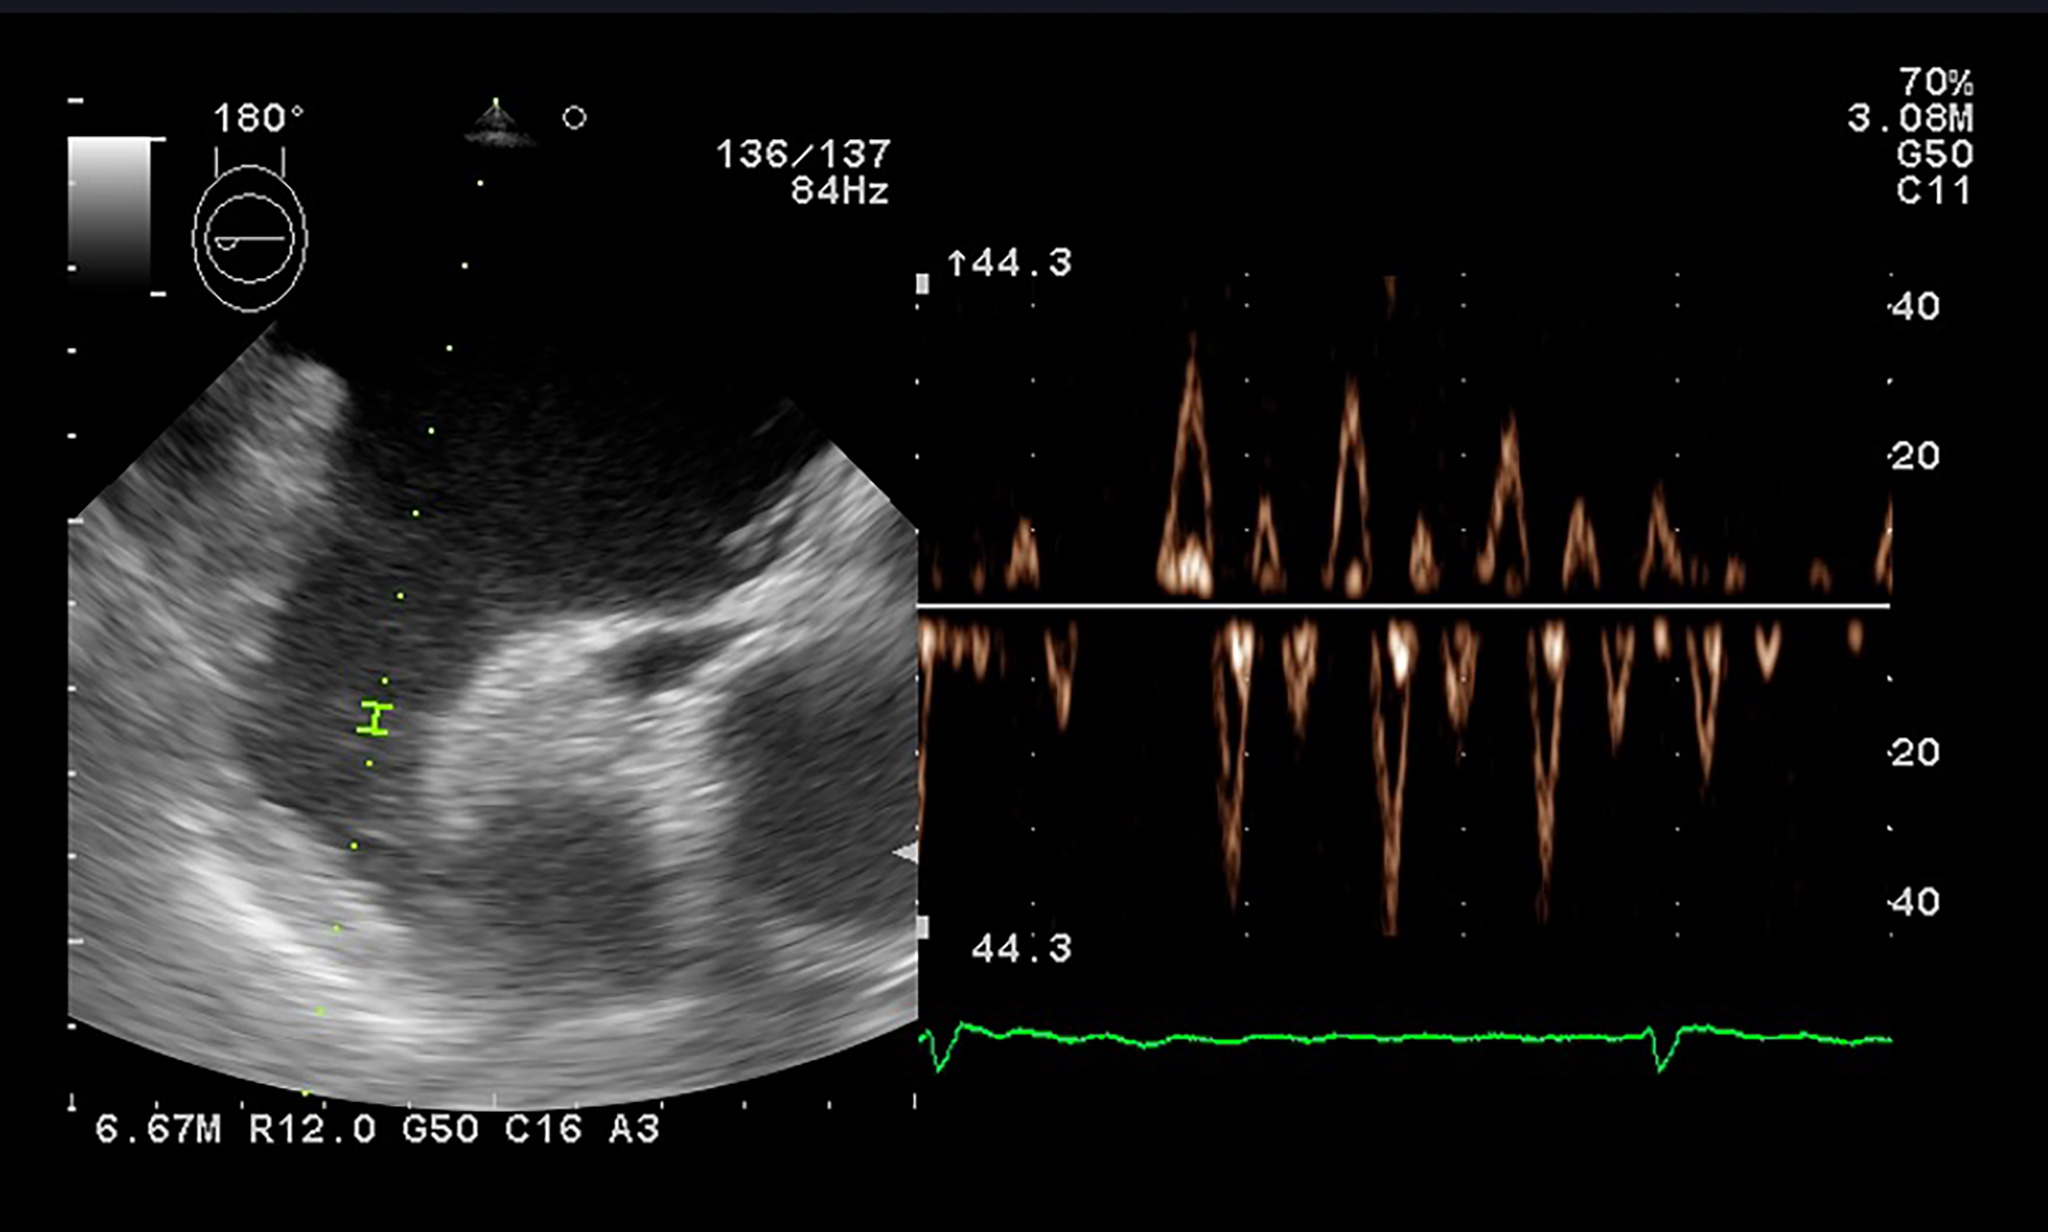

reflect the true LA size, and three-dimensional echocardiography (3D-E) should be

superior for accurate measurement. Atrial volumes by 3D-E (Fig. 3) correlate with

2D-E assessment, but values are higher, as 2D-E underestimates LA volumes in

comparison with other imagistic techniques (especially cardiac magnetic

resonance, which is the gold standard). Most studies evaluated LA volumetry using

dedicated left ventricular programs. Though data is still lacking for normal

ranges, a study in healthy volunteers by Badano et al. [38] determined a

maximum LA index volume in 3D-E of 43 mL/m

Fig. 3.

Fig. 3.Left atrium tridimensional volume and function using 3D-E speckle tracking with a dedicated software.